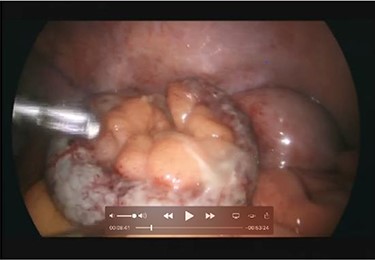

A 66-year-old male patient who had undergone bilateral blepharoplasty 3 days earlier was referred to our acute care surgical service with a 24-hour history of increasing right lower quadrant pain accompanied by nausea, vomiting and anorexia. Clinically he was found to be afebrile with a soft abdomen and focal tenderness at McBurney’s point. Significant laboratory investigations revealed a leukocytosis of 13.0. A CT scan of the abdomen confirmed the diagnosis of appendicitis with an impacted appendicolith at the appendicular outlet and a number of additional appendicoliths distributed along the length of the appendicular lumen (Figs 1–2). The patient was surgically consented for a laparoscopic appendicectomy with intraoperative video recording. At laparoscopy an inflamed and focally necrotic appendix was located coiled over the cecum (Figs 3–4). The appendectomy was completed without complication, and the specimen longitudinally transected in the operating room prior to pathological submission. This revealed four appendicoliths within the lumen, all measuring over 5 mm at their smallest diameter (Fig. 5). Pathology confirmed acute suppurative appendicitis with transmural necrosis, with the appendicoliths described as faeculent in origin. The patient’s post-operative recovery was uneventful.

Intraoperative picture demonstrating the inflamed and coiled appendix with signs of transmural necrosis.